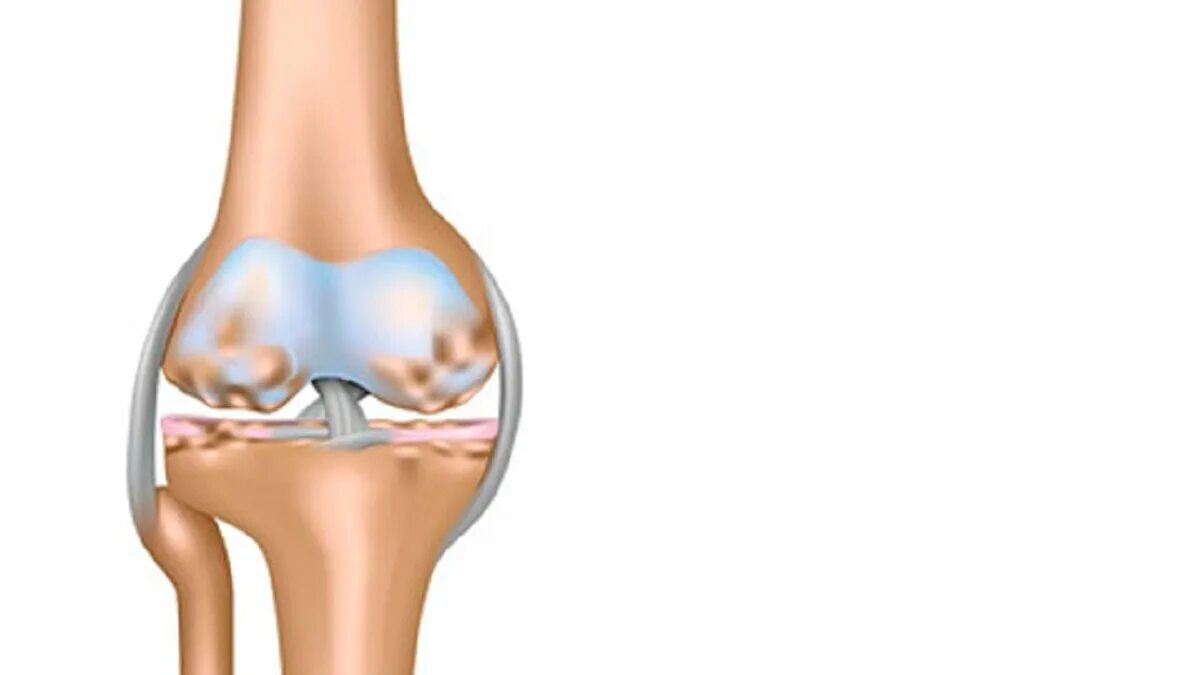

Остеоартрит коленного сустава. остеоартроз коленного сустава. артроз коленного сустава анатомия. остеоартроз коленного сустава мрт.

Артроз или гонартроз коленного сустава. здоровый коленный сустав. артроз коленного сустава лекарства.